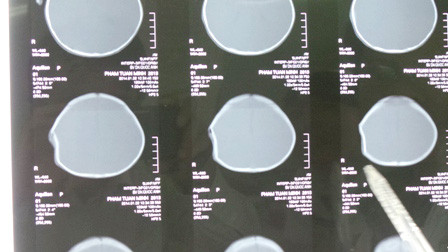

Hình ảnh X-Quang cho thấy vùng sọ của bé Tuấn Minh bị lõm

Hình ảnh X-Quang cho thấy vùng sọ của bé Tuấn Minh bị lõm.

Ngay sau đó, bé Tuấn Minh được chuyển tới bệnh viện Nhi Đồng 2 cấp cứu. Bác sĩ Đặng Ngọc Dũng, khoa Ngoại thần kinh cho biết: “Bệnh nhi Phạm Tuấn Minh nhập viện trong tình trạng hoảng loạn, qua thăm khám lâm sàng ghi nhận cháu bị chấn thương vùng đầu. Do bị tác động mạnh bởi ngoại lực nên hộp sọ vùng đỉnh đầu bên phải của bé bị lõm kín (lõm sọ Ping pong), các kết quả kiểm tra hình ảnh không ghi nhận tổn thương, trên cơ thể cháu không có vết thương hở”.

“Sau khi hội chẩn chúng tôi nhận định các chỉ số sinh hiệu của bé tương đối ổn, tổn thương ở vùng hộp sọ không ảnh hưởng đến sinh mạng bệnh nhi nên quyết định không can thiệp phẫu thuật. Tuy nhiên, cháu sẽ tiếp tục được theo dõi đặc biệt những ngày tới” - BS Dũng nhận định - “Tình huống xảy ra tai nạn của bé Tuấn Minh là đặc biệt nguy hiểm nhưng cháu đã may mắn vì có người dì che chở. Cách đây không lâu, Bệnh viện Nhi Đồng 2 cũng tiếp nhận một trường hợp bị hất văng khỏi xe cấp cứu sau khi va chạm nhưng khi nhập viện bệnh nhân đã tử vong”.

Cũng theo bác sĩ Dũng, ở tuổi đang phát triển như bé Tuấn Minh, vùng hộp sọ bị lõm của cháu sẽ nhanh chóng bình phục và tròn đầy trở lại. Hiện bé đã bú sữa và ăn uống tốt, tuy nhiên khi ngủ cháu hay giật mình hốt hoảng. Bác sĩ chưa thể đánh giá được những ảnh hưởng của tình trạng chấn thương đến sức khỏe của bé về sau.